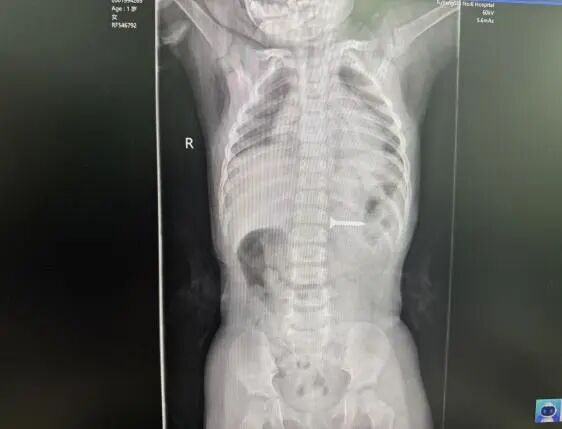

2025年12月31日

阜阳一名3岁幼童

因误吞磁珠

被家长紧急送到

阜阳市妇女儿童医院小儿外科就诊

情况危急

这些小小的磁珠

在消化道内相互吸附

可能造成消化道缺血

穿孔等严重并发症

万幸的是

医院内镜团队

在麻醉科的配合下

紧急实施胃镜探查

15枚磁珠被安全取出